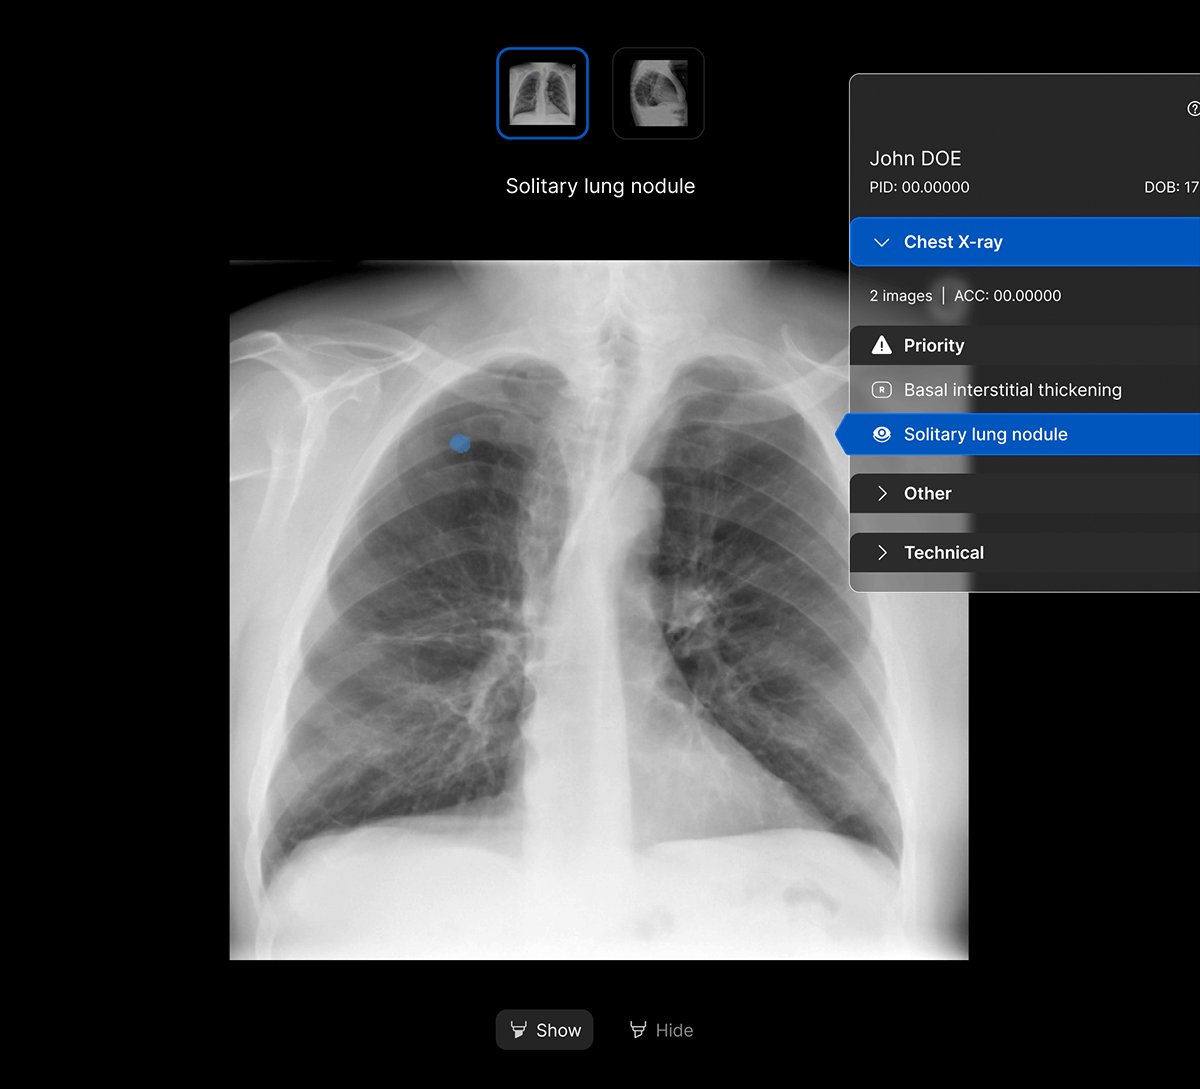

Facilitate accurate diagnoses of complex and subtle cases with AI-decision support identifying up to 124 findings on CXR and 130 findings on CTB.

The user-interface integrates seamlessly with PACS/ RIS, displaying a resizable, no-click overlay window with findings and localisation.

Rapidly identify patients with urgent findings within the radiology worklist with Worklist Prioritisation.

- Detect up to 15 critical and 36 urgent findings on chest X-ray.

- Explainable AI features such as localisation and a confidence bar to improve AI interpretability and clinical decision making.